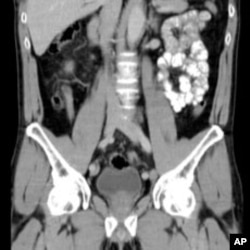

Công nghệ OnGuard Chest X-ray CAD (computer-aided detection) của công ty Riverain phát hiện các cục u bướu hạch nhỏ đáng nghi có thể là dấu hiệu của ung thư phổi giai đoạn sớm giúp cải thiện tỷ lệ sống sót cho các bệnh nhân. (PRNewsFoto/Cleveland Clinic and Riverain Medical)